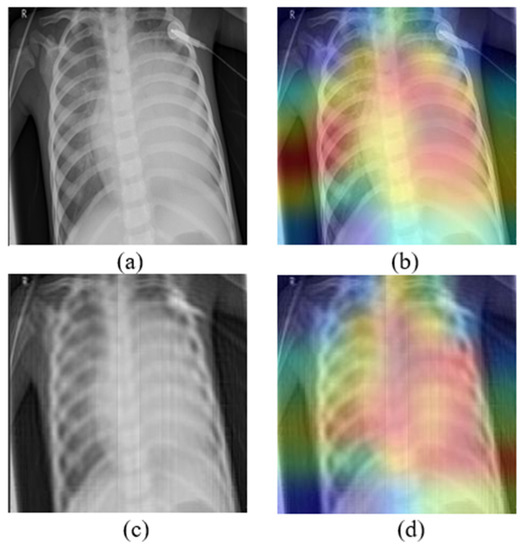

- The image is transformed in a moment set using a discrete orthogonal image moments family.

- Excluding some moments of specific orders, the image is reconstructed producing an approximation.

- The product can be used as an adversarial example to attack every DL model.